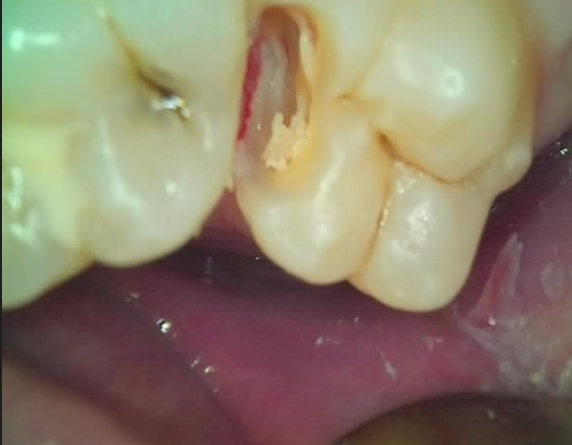

방사선 사진에서 보이는 검정 부위보다 항상 충치는 더 깊게 퍼져 있습니다.

그 이유는, 광물의 소실이 엄청나게 발생한 곳이 검정색으로 비추어지나

그 주변으로 미약하게 퍼진 충치는 사진 상 정상인 것 처럼 나오기 때문입니다.

신경치료를 피하고 싶지만 충치제거를 하고난 후 신경이 노출이 된다면 신경치료가 불가피함을 설명 드리고 치료를 진행 했습니다.

(해당 환자의 신경치료 확률이 90%가 넘어선다는 것을 알고있었지만.. 치과의사 입장에서도 신경치료 같은 깊은 치료는 추 후 질환 발생 시 발치밖에 정답이 없기 때문에 최대한 보존적인 치료를 하고싶어 합니다)

천천히 충치를 제거하고 나니 아니나 다를까, 치아 내부가 단단하지 않은 가죽이 되어 있었고..